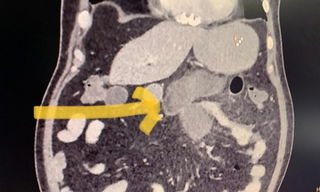

A novel complication of mucormycosis or black fungus has been detected in a city hospital here in which the fungal infection infected the lower intestine of two patients, including a 56-year-old who lost three family members, including his wife, due to Covid....

India has so far reported approximately cases of 8,848 mucormycosis or black fungus, one of the rapidly spreading infections observed in those recovering from Covid-19....